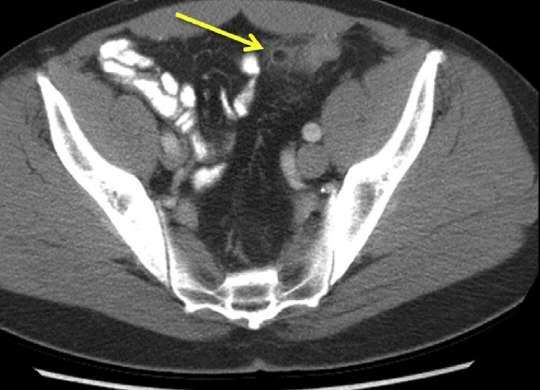

3:肠脂垂炎和网膜梗塞:

肠脂垂炎和网膜梗塞:肠脂垂是沿结肠袋两侧分布的许多小脂肪突起,乙状结肠较多。肠脂垂扭转可造成局部缺血引起炎症。正常的肠脂垂CT上无法看到。肠脂垂炎典型CT表现是;结肠旁脂肪密度结节,边缘局限增高(腹膜炎症增厚可能),伴有中心高密度灶(血栓可能)。

网膜梗塞可能的原因有肥胖、创伤、近期手术史或剧烈活动等。CT表现:网膜不均匀密度脂肪肿块。与肠脂垂炎相比,两者CT表现类似,前者病灶范围大(大于5cm),无中心密度增高灶。两者不易区分时可统称为“腹腔局灶性脂肪坏死”。肠脂垂炎多发生在左下腹,网膜梗塞多见右上及下腹。

肠脂垂炎和网膜坏死是自限性疾病,保守治疗即可。CT检查可明确诊断,避免过度治疗